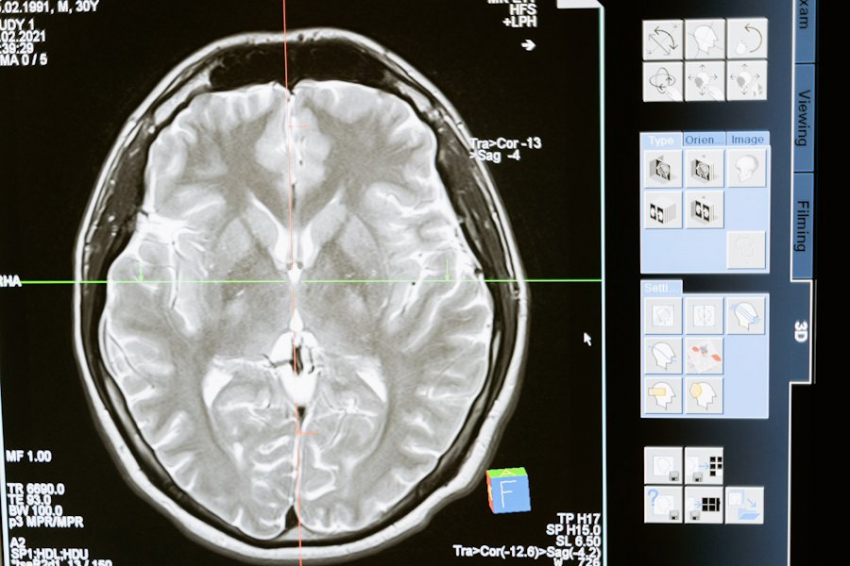

Фото из открытых источников

В Институте передовых информационных технологий Тульского государственного педагогического университета им. Л. Н. Толстого планируют в 2025 году завершить работу над устройством, призванным помочь в реабилитации больных с различными травмами и патологиями головного мозга.

Молодой ученый сосредоточил усилия над системой, распознающей низкочастотные волны мозговой активности посредством аппарата электроэнцефалографии (ЭЭГ). В сообщении пресс-службы Института сказано, что в планах Франчука и его коллег завершить разработку системы уже в следующем году.